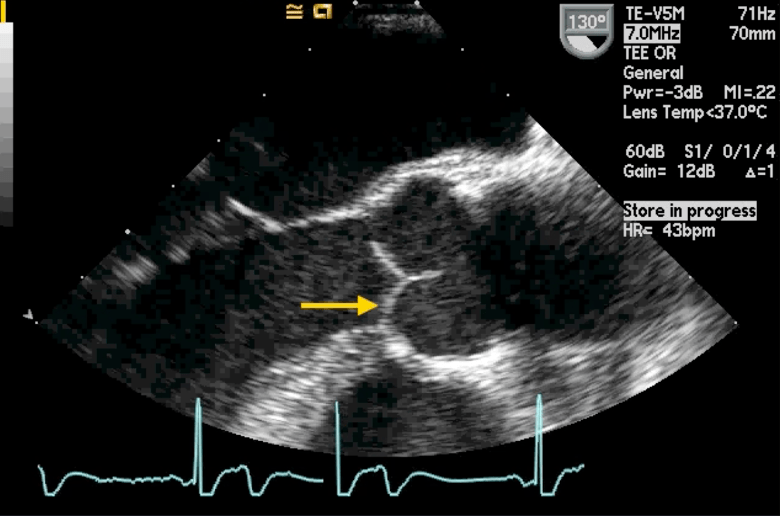

The implanted medical device below

What is a mitra leadless cardiac pacemaker?